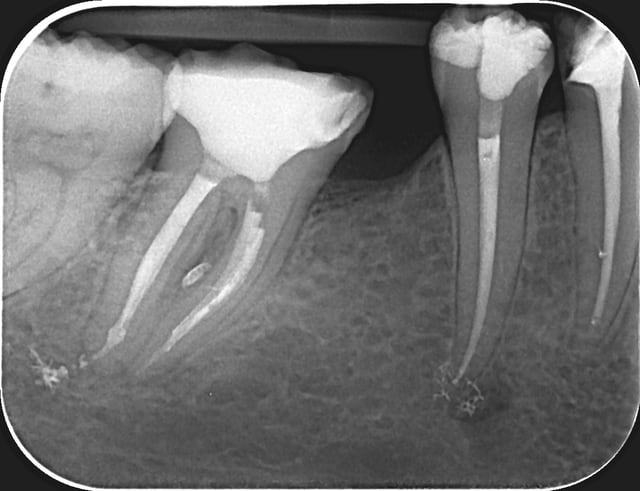

46 - fig 1,2 situation initiale

Fase du traitement: seule visite 2h

- percussion - positive

- teste du vitalité - négative

NaOCl 5% - l'irrigation et l'activation par ultrasons

chaud condensation de gutta-percha

build-up

Apres obturation - fig.3,4